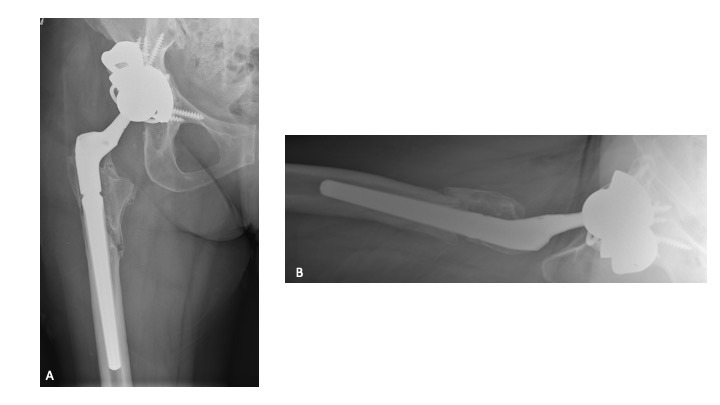

A 63-year-old female presented with recurrent THA instability - verbal consent was obtained for this report. She underwent L2-S1 posterior stabilization with L2-L3 anterior lumbar interbody fusion in May 2002 (Figure 1) and an uncomplicated right THA in April 2007. (Figures 2a-b) Five years following primary THA (July 2011), the patient sustained her first THA dislocation, which was treated with a closed reduction. Between 2011 and 2018, the patient had seven repeat episodes of hip instability – in 2012, one was complicated by a peri-prosthetic femur fracture requiring three revisions and reconstruction with a trochanteric claw plate. She was subsequently diagnosed with a prosthetic joint infection (PJI) which required an antibiotic spacer and subsequent re-implantation three months later. (Figures 3a-b) Following treatment of initial instability and femur fracture, the implants included a size 16 standard taper femoral stem and a 50-mm acetabular shell with 32-mm liner.

Twelve-weeks following re-implantation (2018), the patient experienced recurrent THA instability and was transitioned to our care for definitive treatment. At this time, the patient had a BMI of 24.22 kg/m2 and a past medical history of hypertension, rheumatoid arthritis, gastroparesis, hypothyroidism, and iron deficiency anemia. Relevant prescription medications included calcium carbonate, cholecalciferol, cyclobenzaprine, diltiazem, gabapentin, levothyroxine, and lisinopril. In August 2018, the patient underwent right THA acetabular revision with a porous titanium acetabular shell (56-mm) and dual mobility acetabular liner (44-mm), with four screws (30-mm x 2; 25-mm x 2) for adjuvant fixation. The existing stem was well-fixed and left in place, and a 44-mm/28-mm (+6) ceramic taper sleeve head was impacted. (Figures 4a-b) The patient followed a normal post-operative course and was ambulating pain free without assistance.